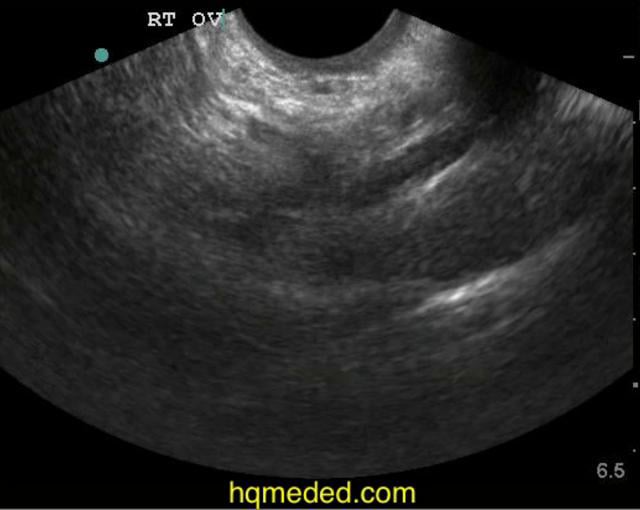

Pelvic ultrasound showing large right ovarian cyst. Download

Pelvic ultrasound showing large right ovarian cyst. Download Pelvic Examination For Ovarian Cyst Describe the pathophysiology of the different types of ovarian cysts. An ultrasonographic examination of the pelvis should be obtained if a patient is thought to have a pelvic mass on clinical examination. Depending on the size of. A cyst on your ovary can be found during a pelvic exam or on an imaging test, such as a pelvic ultrasound. If. Pelvic Examination For Ovarian Cyst.